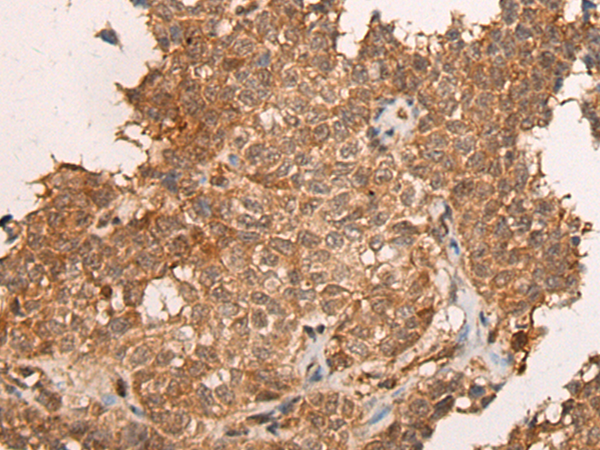

IHC positive control: |

Human thyroid cancer and human ovarian cancer |